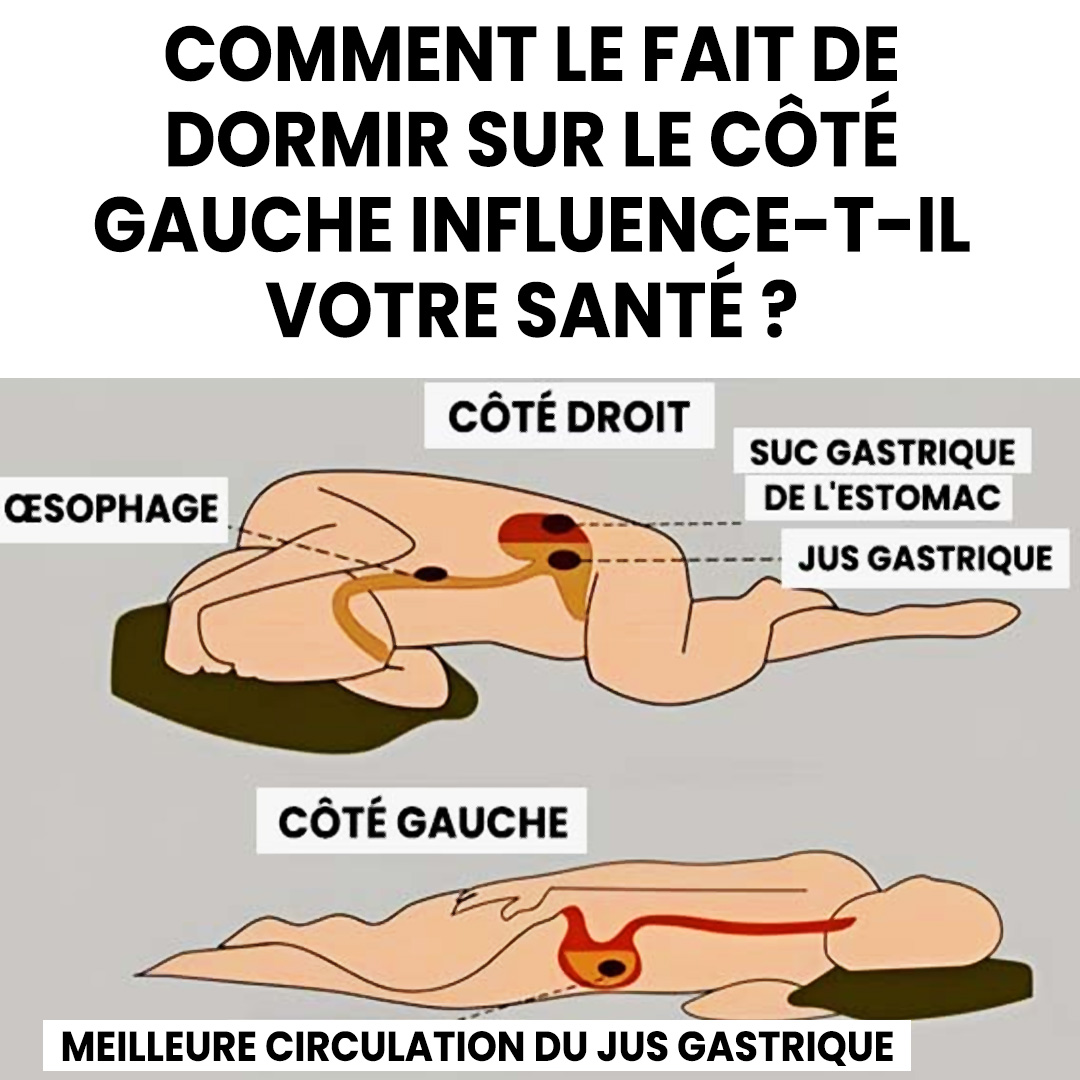

Une aide naturelle pour la digestion et les reflux

Vous souffrez parfois de brûlures d’estomac après le dîner ? Dormir sur le côté gauche peut aider à soulager le reflux acide.

Cette position maintient l’estomac en dessous de l’œsophage, limitant la remontée des sucs gastriques vers la gorge.

Grâce à la gravité, les acides restent bien à leur place, ce qui réduit les sensations de brûlure ou d’amertume nocturne.

Mais ce n’est pas tout : cette posture favorise également une meilleure digestion.

L’estomac et le pancréas se placent dans une position optimale pour libérer leurs enzymes digestives.

Résultat : une digestion plus fluide, moins de ballonnements et un réveil plus léger.